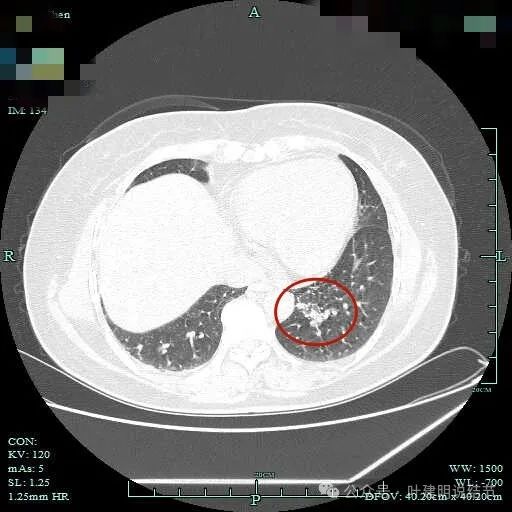

到这层面,聚拢性较前明显,密度显杂乱。

磨玻璃成分更明显,实性成分也明显,实性部分收缩力不强,表面不平整,感觉边缘毛糙。